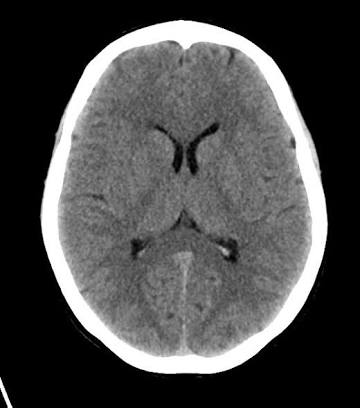

For the physician, he does an objective assessment to confirm the symptoms stated by the patient or the relative and examines the patient thoroughly. Then send for an urgent Brain CT scan which is the investigation of choice.

CT scan is an advanced form of Xray.

It shows if there’s a stroke, the location of the occlusion and the type of stroke. Other imaging like MRI can also be done.

The Physician will also look out for the likely cause of the stroke by asking the relevant questions and sending for some investigations depending on the likely cause.